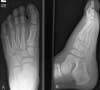

A 7-year-old boy is brought to the pediatrician's office by his mother. The child reportsa 1-day history of acute left foot pain. He had been playing with friends the previousday when he dropped a weight on his left foot. He was wearing shoes at the time. Thefoot has been tender for the past 24 hours, and it is now swollen (Figure 1). The childis not limping.

The x-ray films taken on the initialvisit are as shown (Figure 2). Theanteroposterior view (A) is normal;however, the lateral view (B) is abnormal.Minimal soft tissue swelling,consistent with a history of trauma, isnoted. There is no fracture or periostealelevation of the cuneiform ormetatarsal bones.